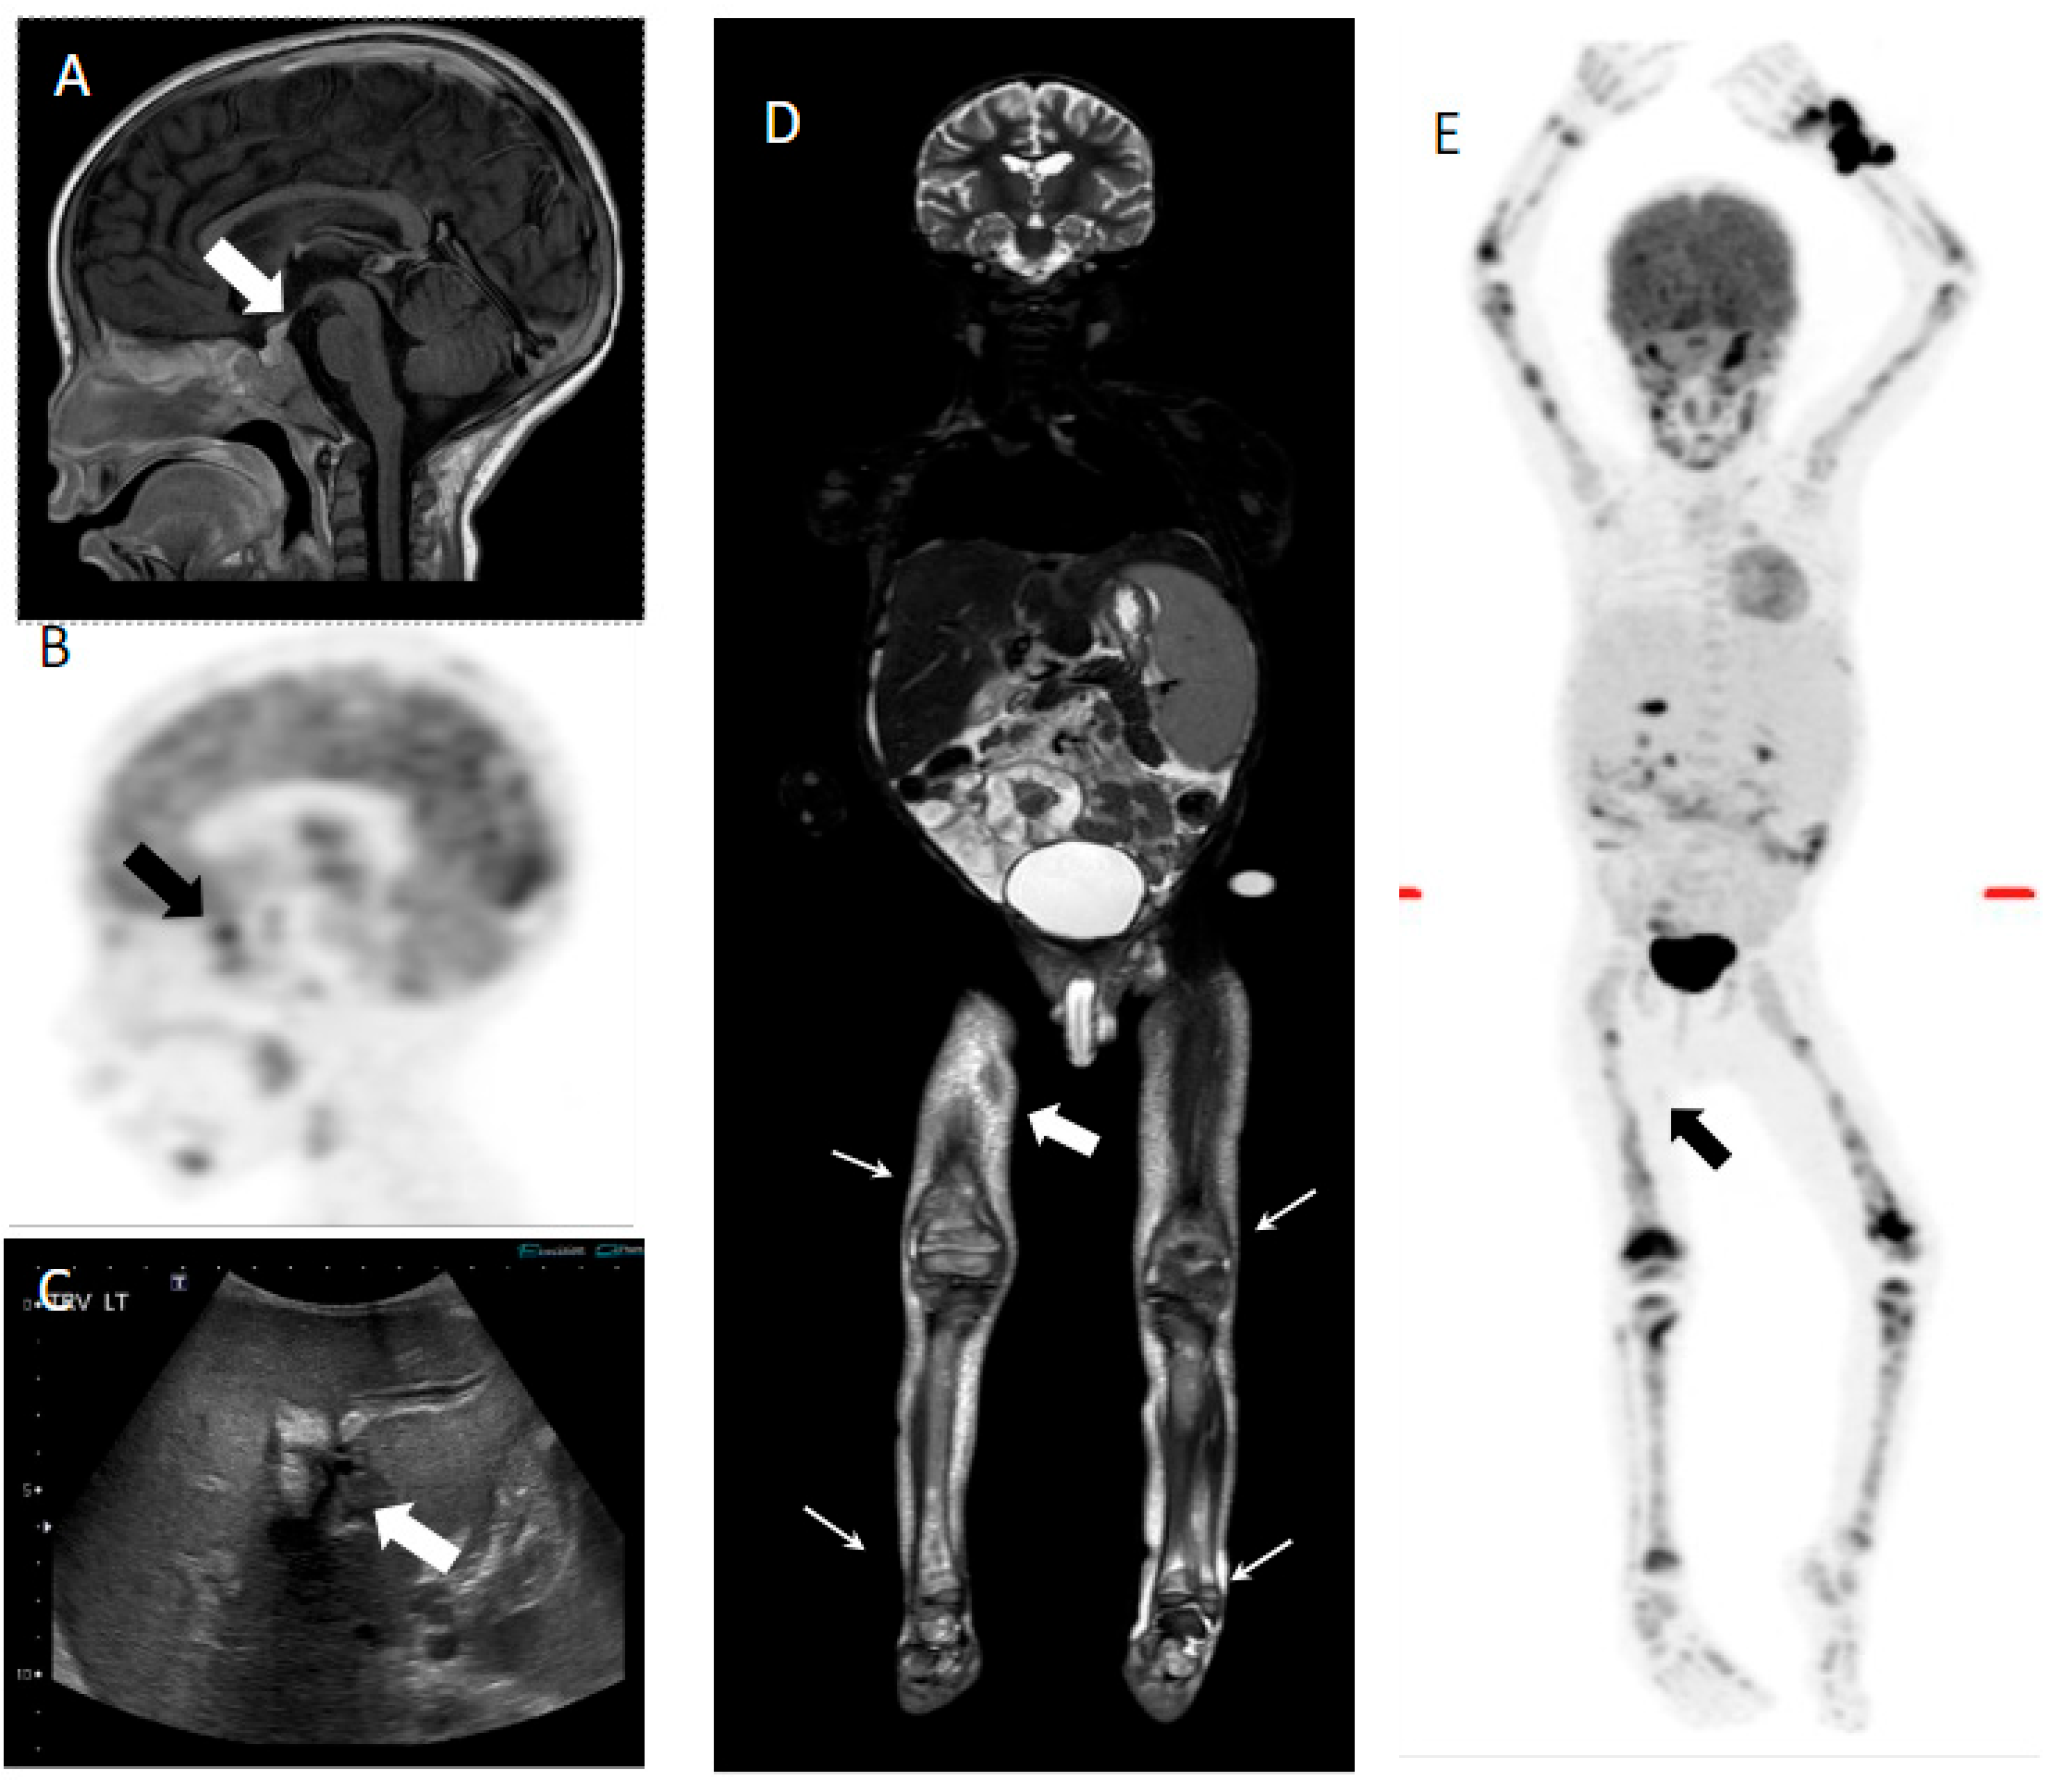

3.1.1. Identification of LCH Lesions at Diagnosis by PET Scans

3.1.2. Re-Staging or Assessment of Disease Reactivation by PET Scans

3.1.3. Assessment of Response to Therapy by PET Scans